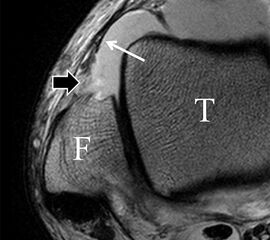

Zu Fehlinterpretationen eines intakten LFTA führt unter Umständen das unmittelbar kaudal des LFTA parallel verlaufende Ligamentum talocalcaneum laterale (Abb. 9 a). Dieses kann bei Verwendung von Schichtdicken um die 3 mm trotz Ruptur des LFTA durch Volumenteileffekte mit Anschnittsphänomenen einen intakten Bandverlauf vortäuschen.

Eine Ursache der falschen Diagnose einer LFTA-Ruptur ist die Fehlinterpretation der physiologische Bandlücke zwischen dem LFTA und der vorderen Syndesmose als traumatischer Banddefekt (Abb. 9 b).

Die Interpretation pathologischer Veränderungen sollte daher immer multiplanar unter Verwendung möglichst dünner Schichtdicken und hoher Ortsauflösungen erfolgen, um Fehldiagnosen zu vermeiden.